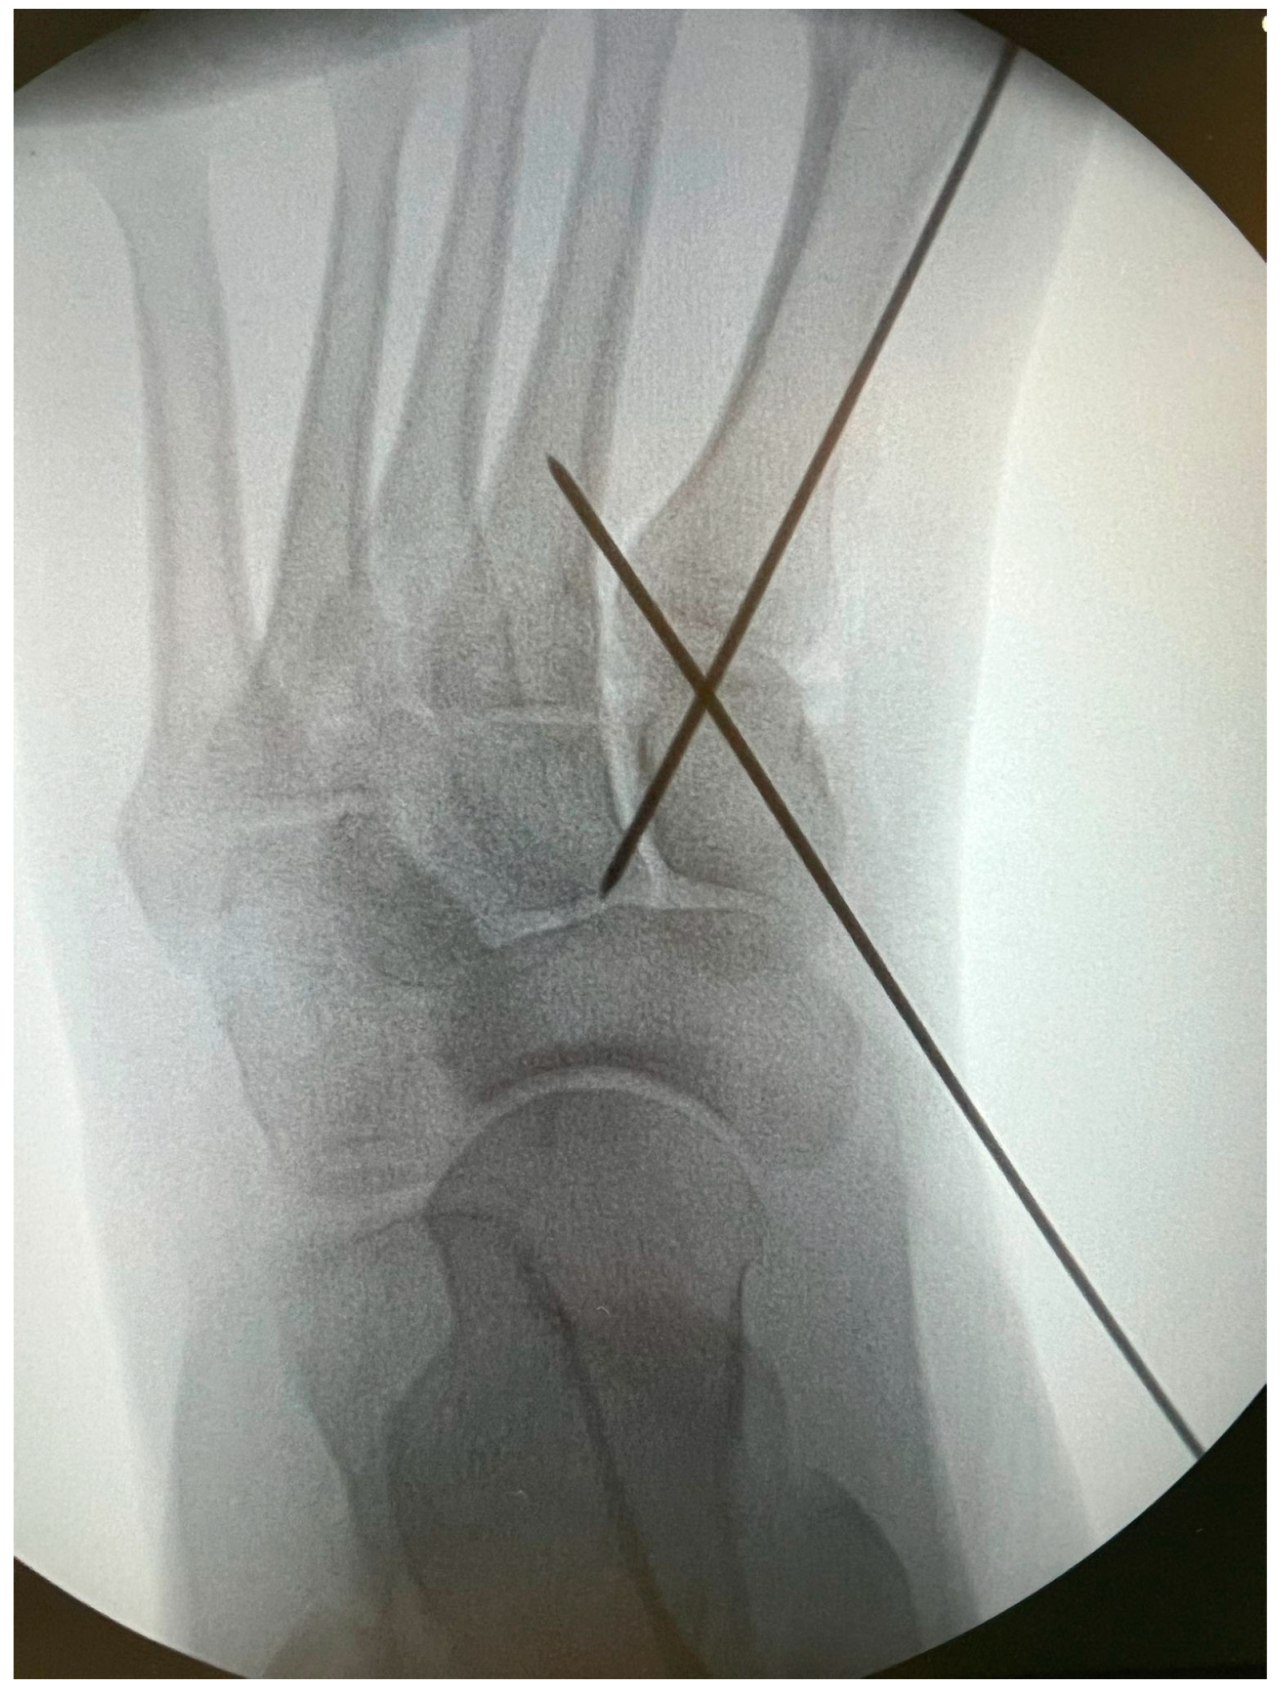

Minimally Invasive Lapidus Arthrodesis Associated with Distal Osteotomy of M1: A Combined Procedure for Hallux Valgus Correction

2. Materials and Methods